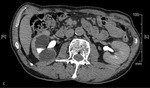

Proces zapalny obejmujący torbiel nerki może dać bardzo różnorodny obraz (zmiana charakteru płynu w obrębie torbieli znajduje odbicie w badaniach obrazowych). Obwodowe wzmocnienie pokontrastowe może wręcz potwierdzać występowanie ropnia.1 Tej koncepcji przeczy jednak stan kliniczny pacjenta i brak odchyleń od normy w badaniach laboratoryjnych. Rak nerkowokomórkowy przeważnie jest guzem o charakterze litym, jednak w ok. 20% przypadków może zawierać także elementy torbielowate.1 Obecność wzmocnienia obwodowego w fazie pokontrastowej badania TK, zwłaszcza rozmieszczonego nieregularnie, zawsze musi budzić podejrzenie rozrostu nowotworowego. U pacjenta, którego przypadek jest opisywany, na podstawie wyników badania histopatologicznego rozpoznano raka nerkowokomórkowego. Innym przykładem guza nowotworowego o charakterze torbielowatym, który może występować w obrębie nerki, jest torbielakogruczolak, znany także jako nerczak torbielowaty wielokomorowy. Guz najczęściej stwierdza się u małych chłopców i kobiet w wieku 40-70 lat (inaczej niż w prezentowanym przypadku). Składa się on z licznych torbieli wypełnionych śluzowatą treścią. W obrębie guza często występują zwapnienia (szacuje się, że w 10-50% przypadków), natomiast obszary krwotoczne lub martwicy, zazwyczaj obserwowane w rakach nerkowokomórkowych, w nerczakach torbielowatych są rzadkie. Kielichy i miedniczka nerki bywają modelowane przez torbiele, które nie komunikują się z układem wydalniczym. Po podaniu środka kontrastowego wzmocnieniu ulega lita część guza.1 Typowy obraz TK torbielakogruczolaka nerki zaprezentowano na rycinie 3A-C.